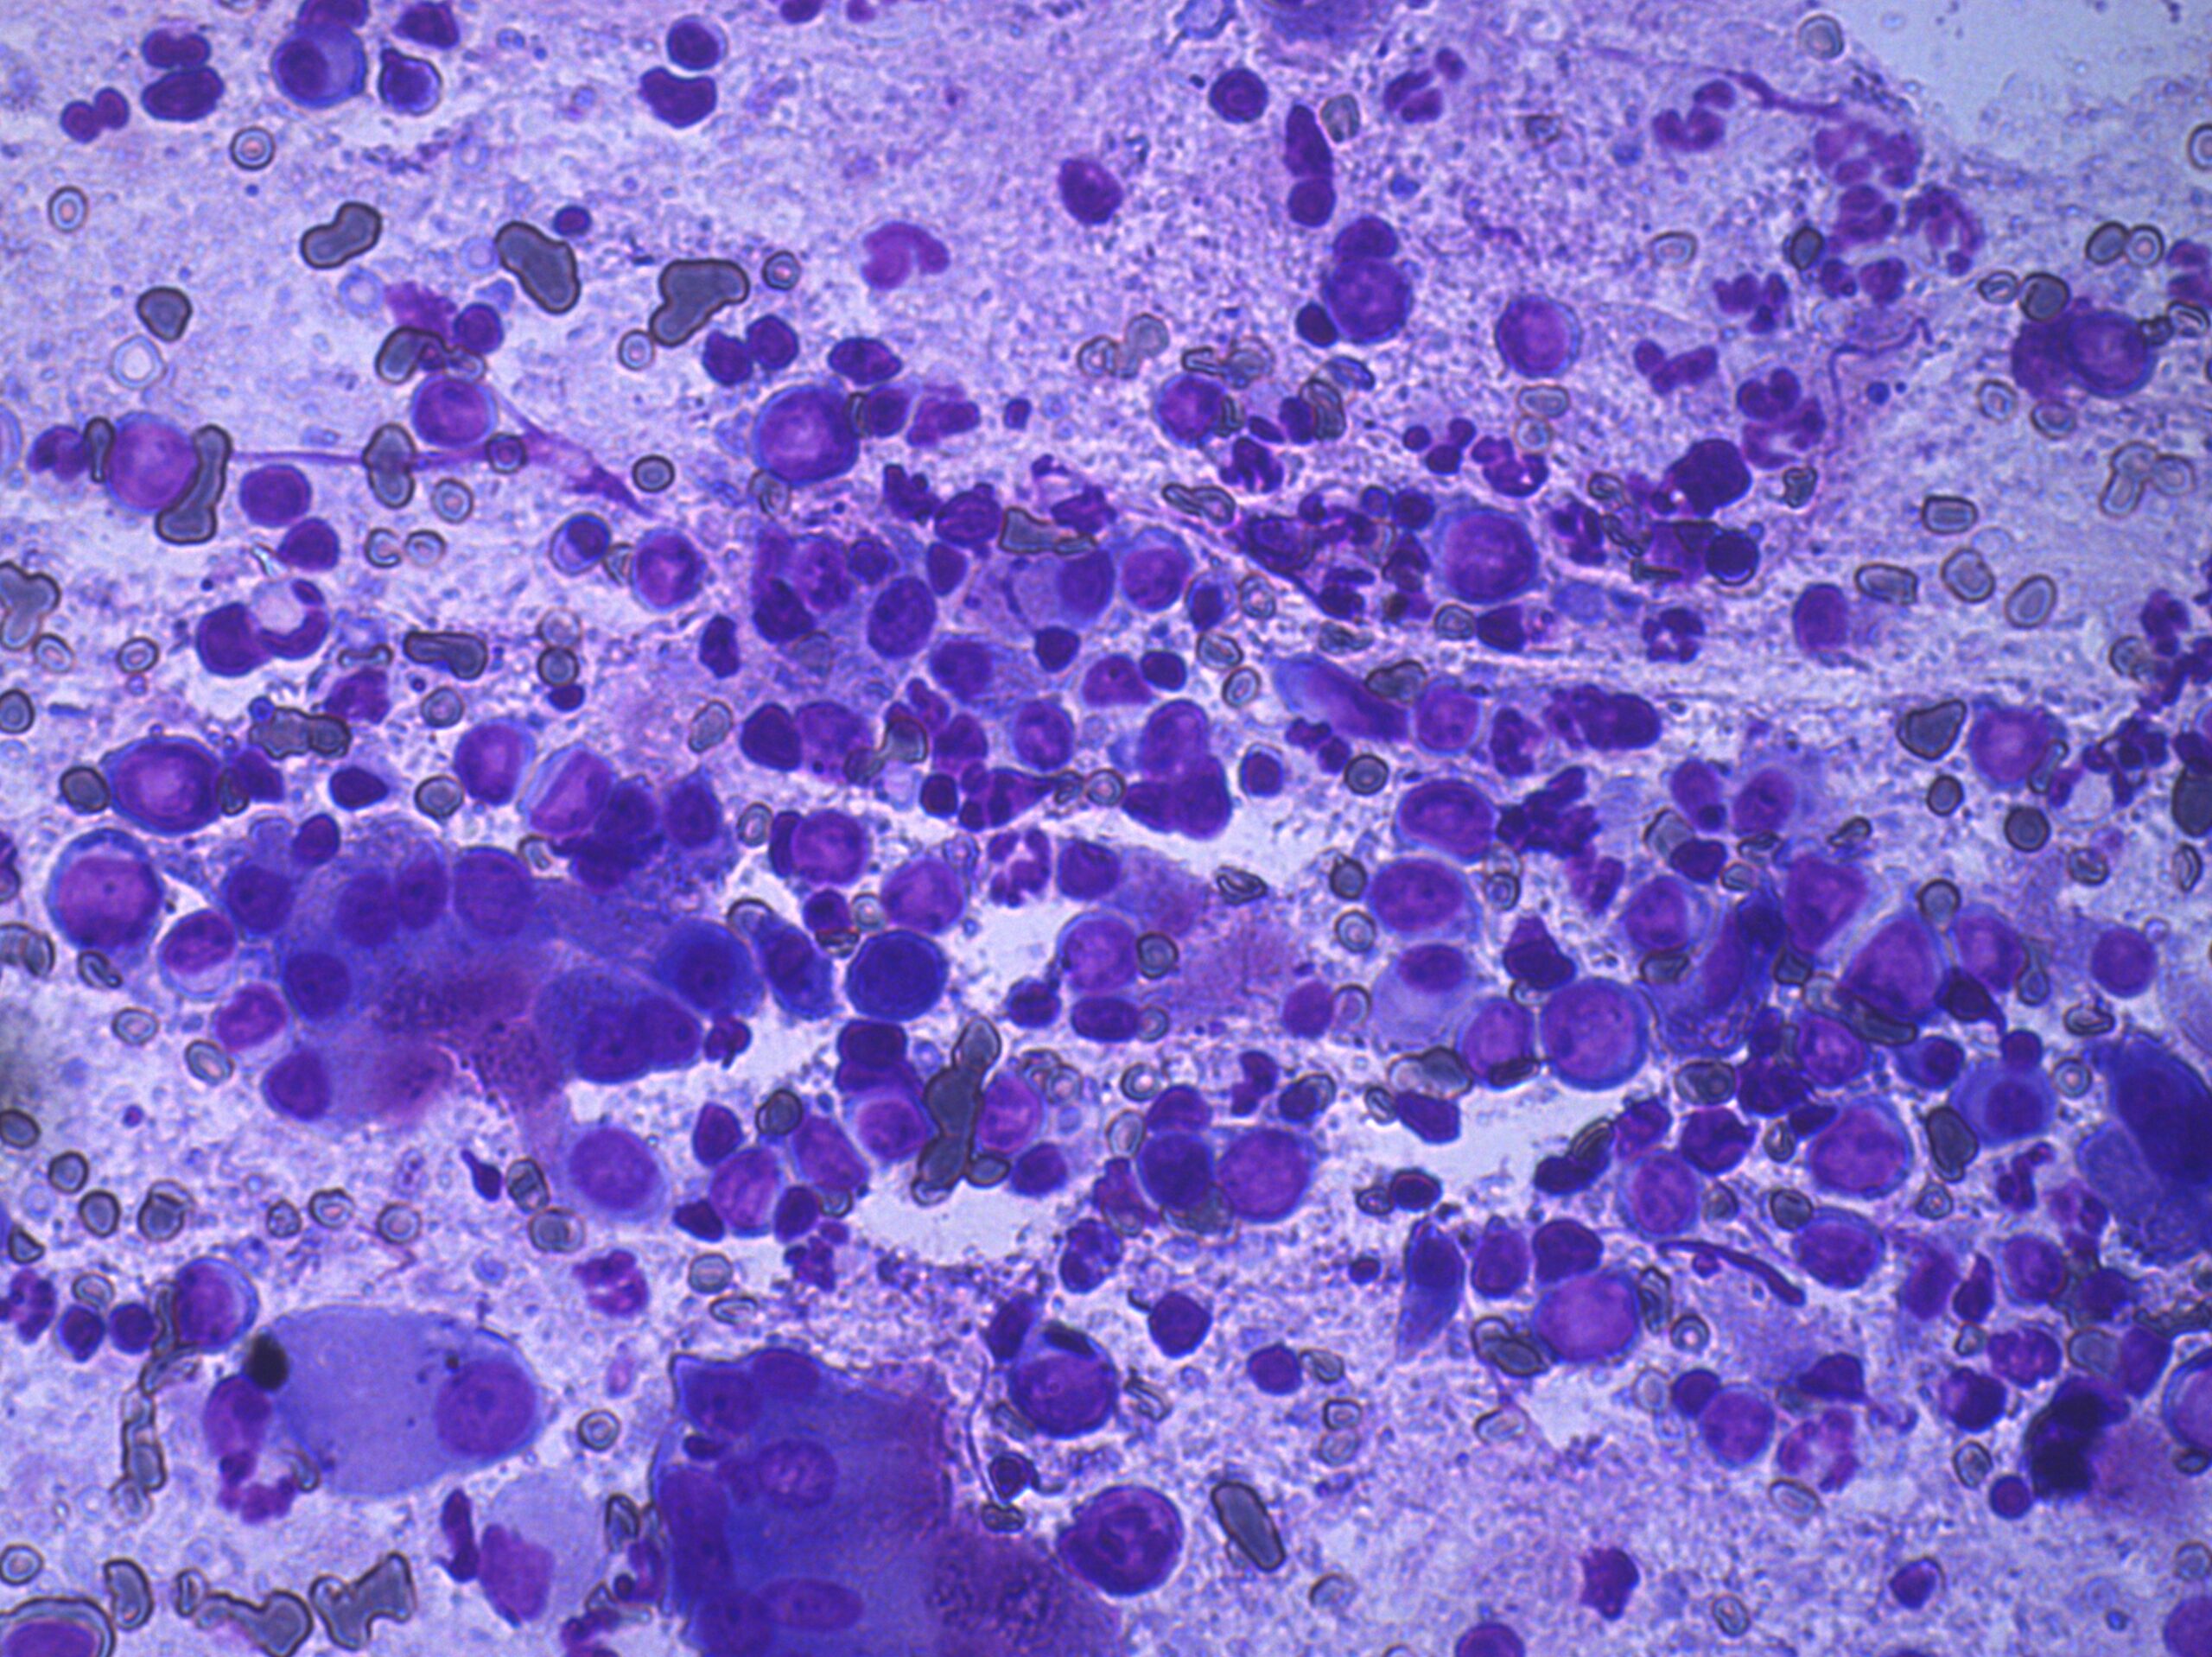

診断と治療

CT撮影と組織生検にて大細胞性リンパ腫と診断され、放射線治療と抗がん剤治療の提案をしました。相談の結果抗がん剤治療を行うこととなり6カ月の抗がん剤治療(CHOPプロトコル)を行いました。